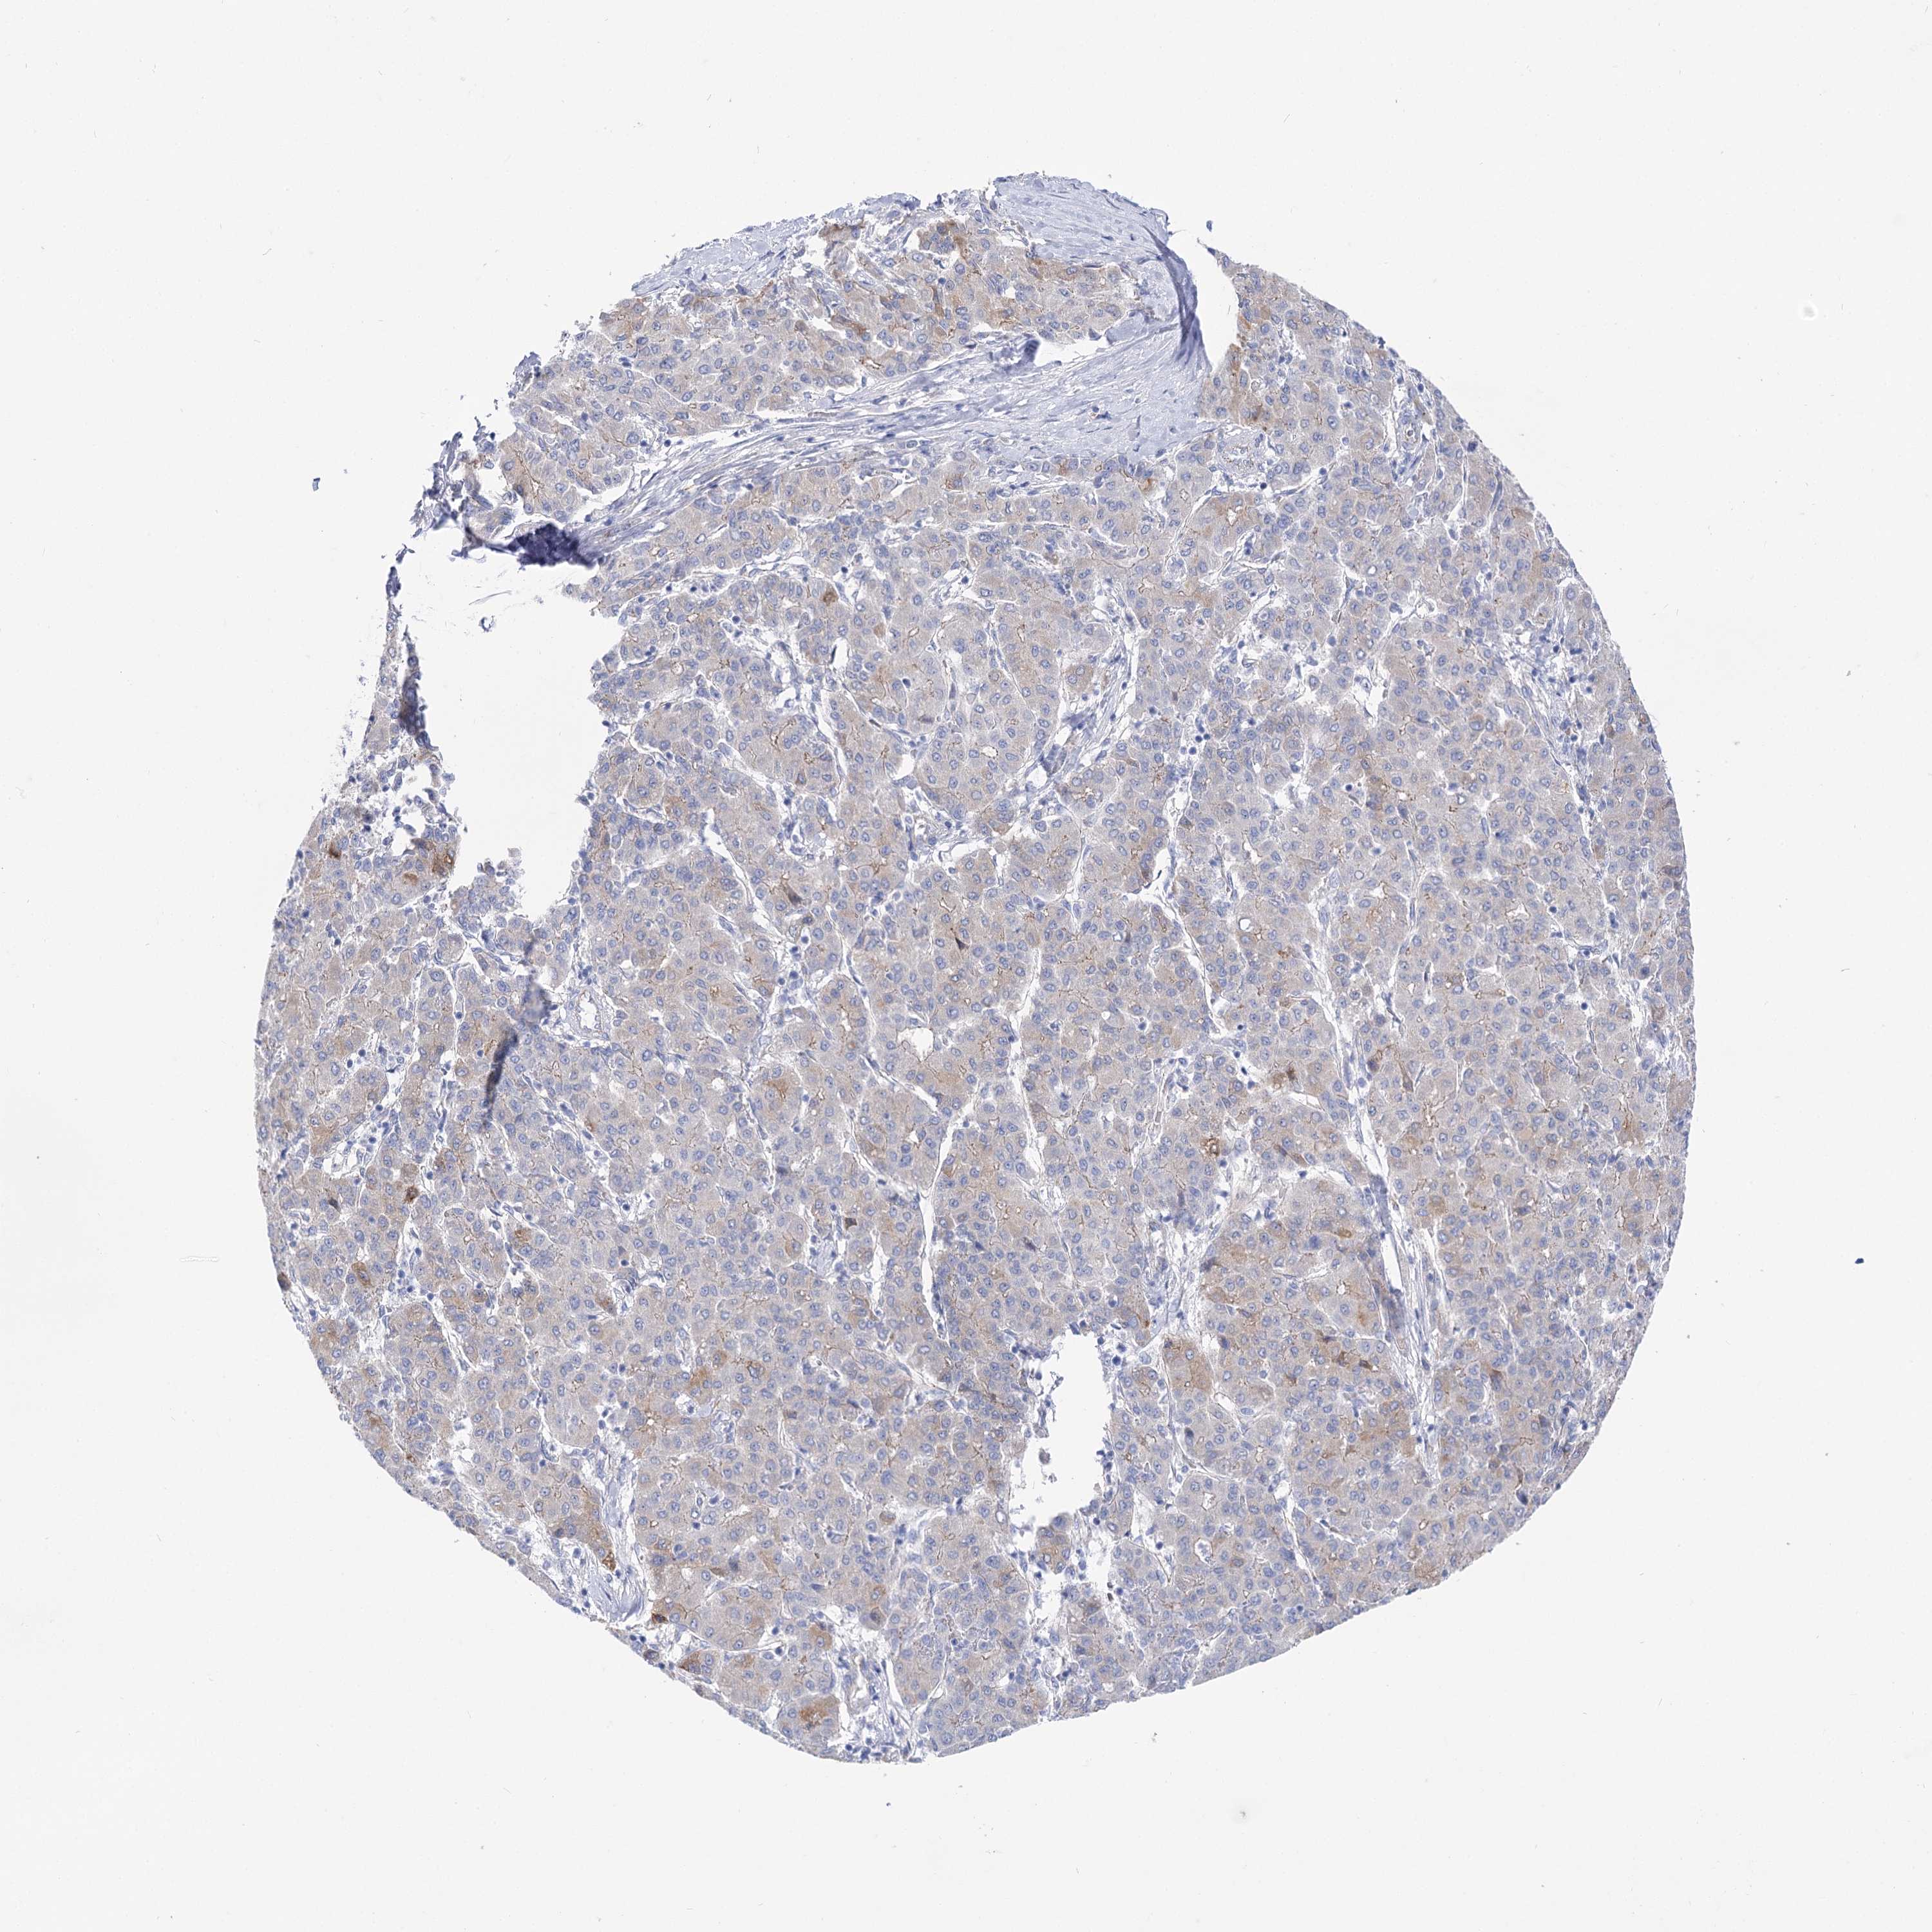

LIVER CANCER - Protein expressioni

A mouse-over function shows sample information and annotation data. Click on an image to view it in a full screen mode. Samples can be filtered based on level of antibody staining by selecting one or several of the following categories: high, medium, low and not detected. The assay and annotation is described here.

Note that samples used for immunohistochemistry by the Human Protein Atlas do not correspond to samples in the TCGA dataset.

Antibody stainingi

Antibody staining in the annotated cell types in the current human tissue is reported as not detected, low, medium, or high, based on conventional immunohistochemistry profiling in selected tissues. This score is based on the combination of the staining intensity and fraction of stained cells.

Each image is clickable and will lead to virtual microscopy that enables deeper exploration of all samples and also displays staining intensity scores, fraction scores and subcellular localization as well as patient and tissue information for each sample.

Antibody HPA037953

Antibody HPA037954

Staining

High

Medium

Low

Not detected

Intensity

Strong

Moderate

Weak

Negative

Quantity

>75%

75%-25%

<25%

None

Location

Nuclear

Cytoplasmic/membranous

Cytoplasmic/membranous,nuclear

Cholangiocarcinoma

Carcinoma, Hepatocellular, NOS